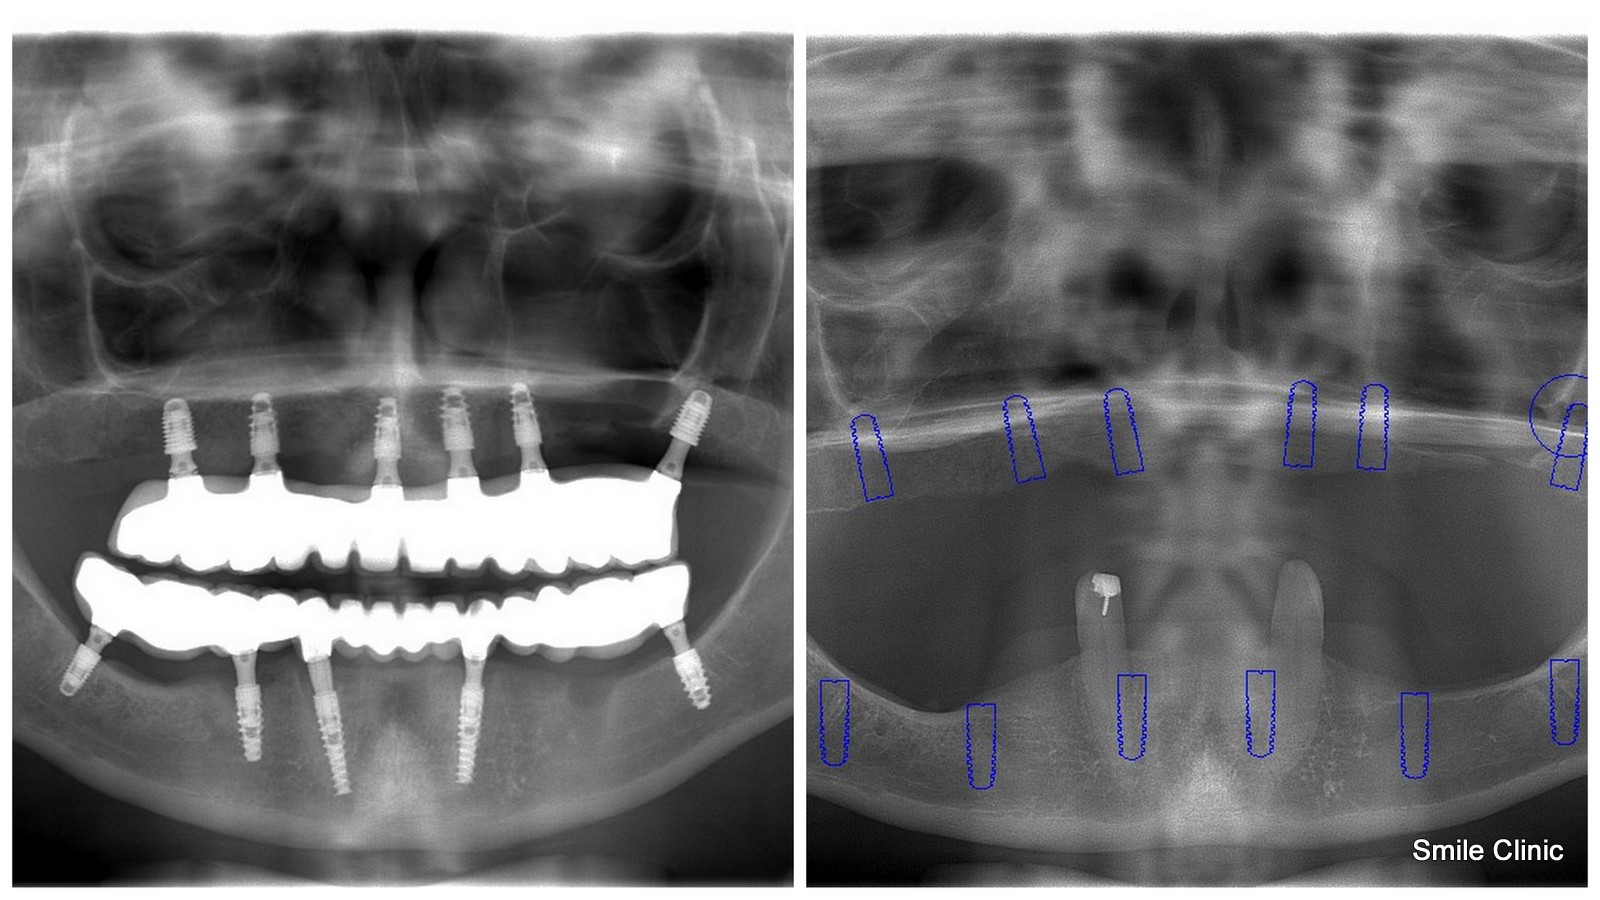

As you can see from the X-ray in this post, this soon-to-be-wed lady had almost no existing teeth whatsoever, and was wearing false teeth dentures. Of course, like most of us, she felt very uncomfortable wearing them.

Dental Holiday in Slovakia offers a same day replacement of the whole upper and lower jaw with a semi-permanent bridge based on dental implants (11 were used in this case to add extra strength support in the thin amount of jawbone available for stable bridge support).

The patient then returned some months later after a period of healing for impression and a final fixed tooth bridge for both the upper and lower jaw.